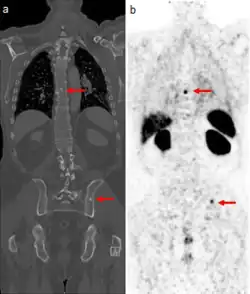

The extent of cancer spread is assessed by MRI or PSMA scan – a positron emission tomography (PET) imaging technique where a radioactive label that binds the prostate protein prostate-specific membrane antigen is used to detect metastases distant from the prostate.[30][24] CT scans may also be used, but are less able to detect spread outside the prostate than MRI. Bone scintigraphy is used to test for spread of cancer to bones.[30]

After prostatectomy, PSA levels drop rapidly, reaching very low or undetectable levels within two months. Radiotherapy also substantially reduces PSA levels, but more slowly and less completely, with PSA levels reaching their nadir two years after radiotherapy.[53] After either treatment, PSA levels are monitored regularly. Up to half of those treated will eventually have a rise in PSA levels, suggesting the tumor or small metastases are growing again.[54] People with high or rising PSA levels are often offered another round of radiation therapy directed at the former tumor site. This reduces risk for further progression by 75%.[54] Those suspected of metastases can undergo PET scanning with sensitive radiotracers C-11 choline, F-18 fluciclovine, and F-18 or Ga-68 attached to a PSMA-targeting drug, each of which is able to detect small metastases more sensitively than alternative imaging methods.[55][54]